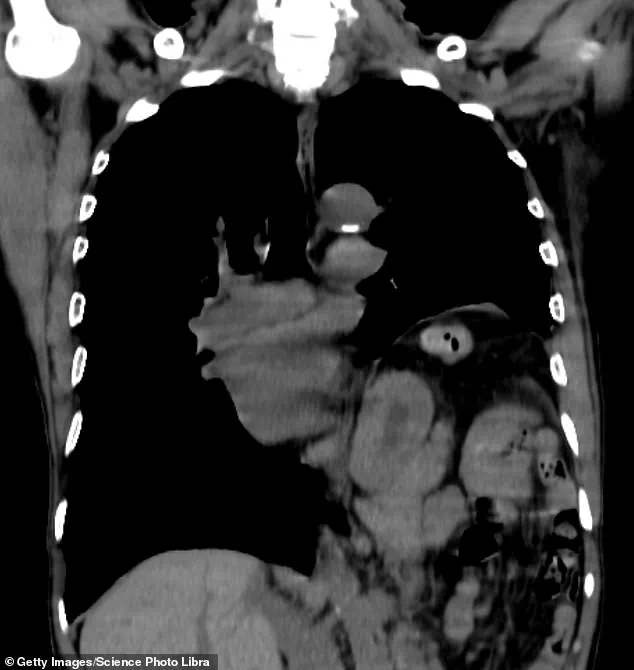

Among the most common physical causes is a hiatus hernia, where the upper part of the stomach protrudes through the diaphragm.

Treatment options range from minimally invasive surgery to manage the hernia to addressing underlying conditions such as tumours, cysts, or neurological disorders like Parkinson’s disease.

In a final attempt to address his condition, Frankie was referred for surgery to repair a hiatus hernia, which his doctor suspected might be exacerbating his hiccups.